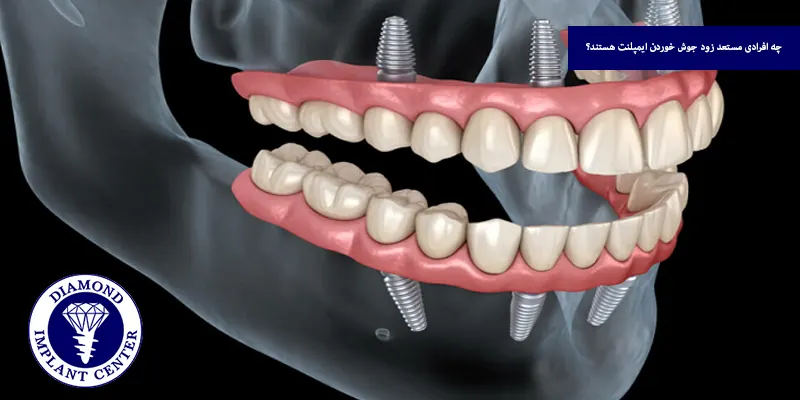

فرایند جوش خوردن ایمپلنت دندان که به آن استئواینتگریشن گفته میشود، به اتصال مستقیم و پایدار پایه تیتانیومی ایمپلنت با استخوان فک اطلاق دارد و این روند چند ماه زمان میبرد و به این صورت است که پایه فلزی در استخوان فک جای گذاری میشود و بدن واکنش طبیعی به ایمپلنت نشان میدهد و سلول های استخوان ساز شروع به ساخت استخوان در اطراف پایه میکنند.

با گذشت زمان، سلول های استخوانی به سطح ایمپلنت میچسبند و آن را به طور طبیعی در استخوان فک تثبیت میکنند، این اتصال پایدار میشود و پایه ایمپلنت دندان به عنوان بخشی از فک عمل میکند.

روند طبیعی جوش خوردن ایمپلنت دندان بین ۳ تا ۶ ماه طول میکشد و در این بازه زمانی، پایه تیتانیومی ایمپلنت به تدریج با استخوان فک پیوند میخورد، فرآیندی که به آن استئواینتگریشن گفته میشود، مدت زمان دقیق این روند به عواملی مانند تراکم استخوان، محل کاشت (فک بالا یا پایین)، وضعیت سلامت عمومی بیمار، نوع ایمپلنت و مراقبتهای بعد از جراحی بستگی دارد، در برخی افراد با شرایط ایدهآل، این زمان ممکن است کوتاهتر و در افراد با مشکلات زمینهای، طولانیتر باشد.

تراکم استخوان یکی از مهم ترین عوامل در موفقیت و سرعت جوش خوردن ایمپلنت دندان است، هرچه تراکم استخوان فک بیشتر باشد، پایه ایمپلنت بهتر در جای خود فیکس میشود و تماس بیشتری با استخوان دارد و این تماس مؤثر، رشد سلول های استخوان ساز را تحریک کرده و فرایند جوش خوردن ایمپلنت با استخوان را تسریع میکند.

در مقابل، استخوانهایی با تراکم کم مانند فک بالا یا در افراد مسن و مبتلا به پوکی استخوان، زمان بیشتری برای ایجاد اتصال پایدار با ایمپلنت نیاز دارند، در این موارد، نیاز به استفاده از پودر استخوان یا تکنیکهای خاص تقویت استخوان است تا شرایط مناسب برای کاشت و جوش خوردن فراهم شود.